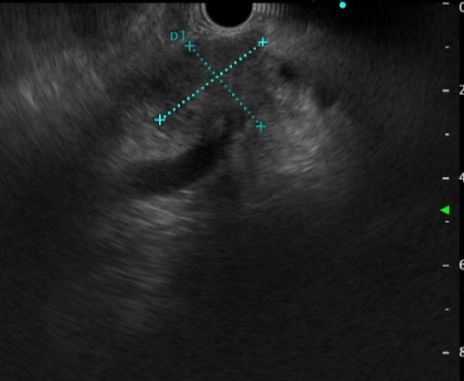

患者,男,58岁,主因“间断进食不畅1月”,就诊于我消化内三科。我院电子胃镜提示:食管下段近贲门处可见巨大隆起性病灶,超声内镜提示:病变起源于固有肌层,最大切面大小约4cmx1.3cm,呈低回声。考虑平滑肌瘤。积极完善相关化验及检查,查无内镜下治疗禁忌症,遂于2023年5月30日行内镜下食管肿物挖出术。